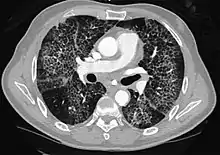

High-resolution CT image showing ground-glass opacities in the periphery of both lungs in a patient with COVID-19 (red arrows). The adjacent normal lung tissue with lower attenuation appears as darker areas.

CT image in patient with COVID-19 showing bilateral ground-glass opacities at the periphery of both lungs.

Ground-glass opacity is among the most common imaging findings in patients with confirmed COVID-19.[16][17] One systematic review found that among patients with COVID-19 and abnormal lung findings on CT, greater than 80% had GGOs, with greater than 50% having mixed GGOs and consolidation.[16] GGOs with mixed consolidation has most often been found in elderly populations.[18] Several studies have described a pattern among initial, intermediate, and hospital discharge imaging findings in the disease course of COVID-19. Most commonly, initial CT imaging reveals bilateral GGOs at the periphery of the lungs. During initial stages, this is most often found in the lower lobes, although involvement of the upper lobes and right middle lobe has also been reported early in the disease course.[16][18] This is in contrast to the two similar coronaviruses, SARS and MERS, which more commonly involve only one lung on initial imaging.[19][20] As the COVID-19 infection progresses, GGOs typically become more diffuse and often progress to consolidation.[11][18] This is sometimes accompanied by the development of a crazy paving pattern and interlobular septal thickening.[18] In many cases the most severe pulmonary CT abnormalities occurred within 2 weeks after symptoms began.[17] At this point, many individuals begin showing resolution of consolidation and GGOs as symptoms improve. However, some patients have worsening symptoms and imaging findings, with further increase in septal thickening, GGOs, and consolidation. These patients may develop lung "white-out" with progression to acute respiratory distress syndrome (ARDS) requiring treatment escalation.[17][21]

Preliminary reports have shown many patients have residual GGOs at time of discharge from the hospital. Due to the novelty of COVID-19, large studies investigating the long-term pulmonary CT changes have yet to be completed. However, long-term pulmonary changes have been seen in patients after recovery from SARS and MERS, suggesting the possibility of similar long-term complications in patients who have recovered from acute COVID-19 infection.[22]